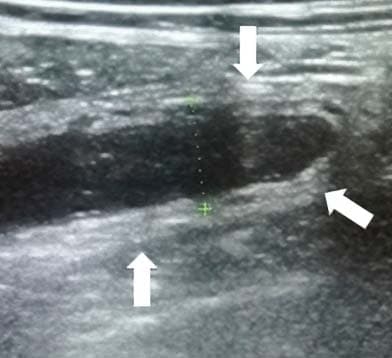

Аппендикс считается расширенным, если под действием компрессии его наружный переднезадний размер, измеренный при поперечном сканировании, более 6 мм (см. рис. 3).

Рисунок 3. Определение диаметра аппендикса.